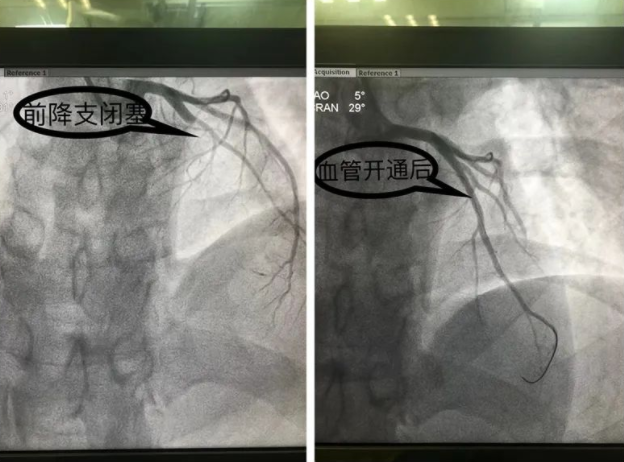

“手术台上,我们造影发现患者前降支在对角支开口后完全闭塞 我们用导丝穿过了闭合段,然后用球囊扩张了狭窄的部位,把血管开通了之后发现是严重的局限性狭窄,狭窄程度达到99%,如果再晚几分钟,基本上很难救过来”彭描宇说道。

手术有惊无险,张先生的血管恢复流通,病情得到控制,随后转入重症病房观察治疗。